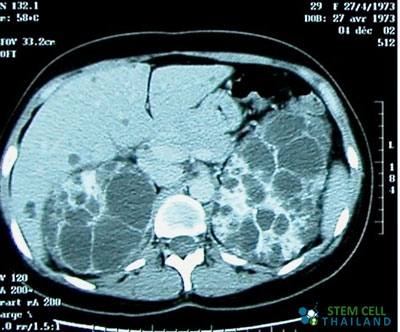

Polycystic kidney disease “PKD” is a medical condition wherein numerous fluid-filled cysts are found to have grown in either or both kidneys. These cysts cause enlargement and, if left untreated, can grow to an abnormal size that can destroy normal kidney structure and affect kidney function that could lead to eventual kidney failure and death

The cysts are mostly benign or non-carcinogenic, as most of them are full of bodily fluids or water. However, their sizes could grow larger than the kidney itself because of continual fluid accumulation.